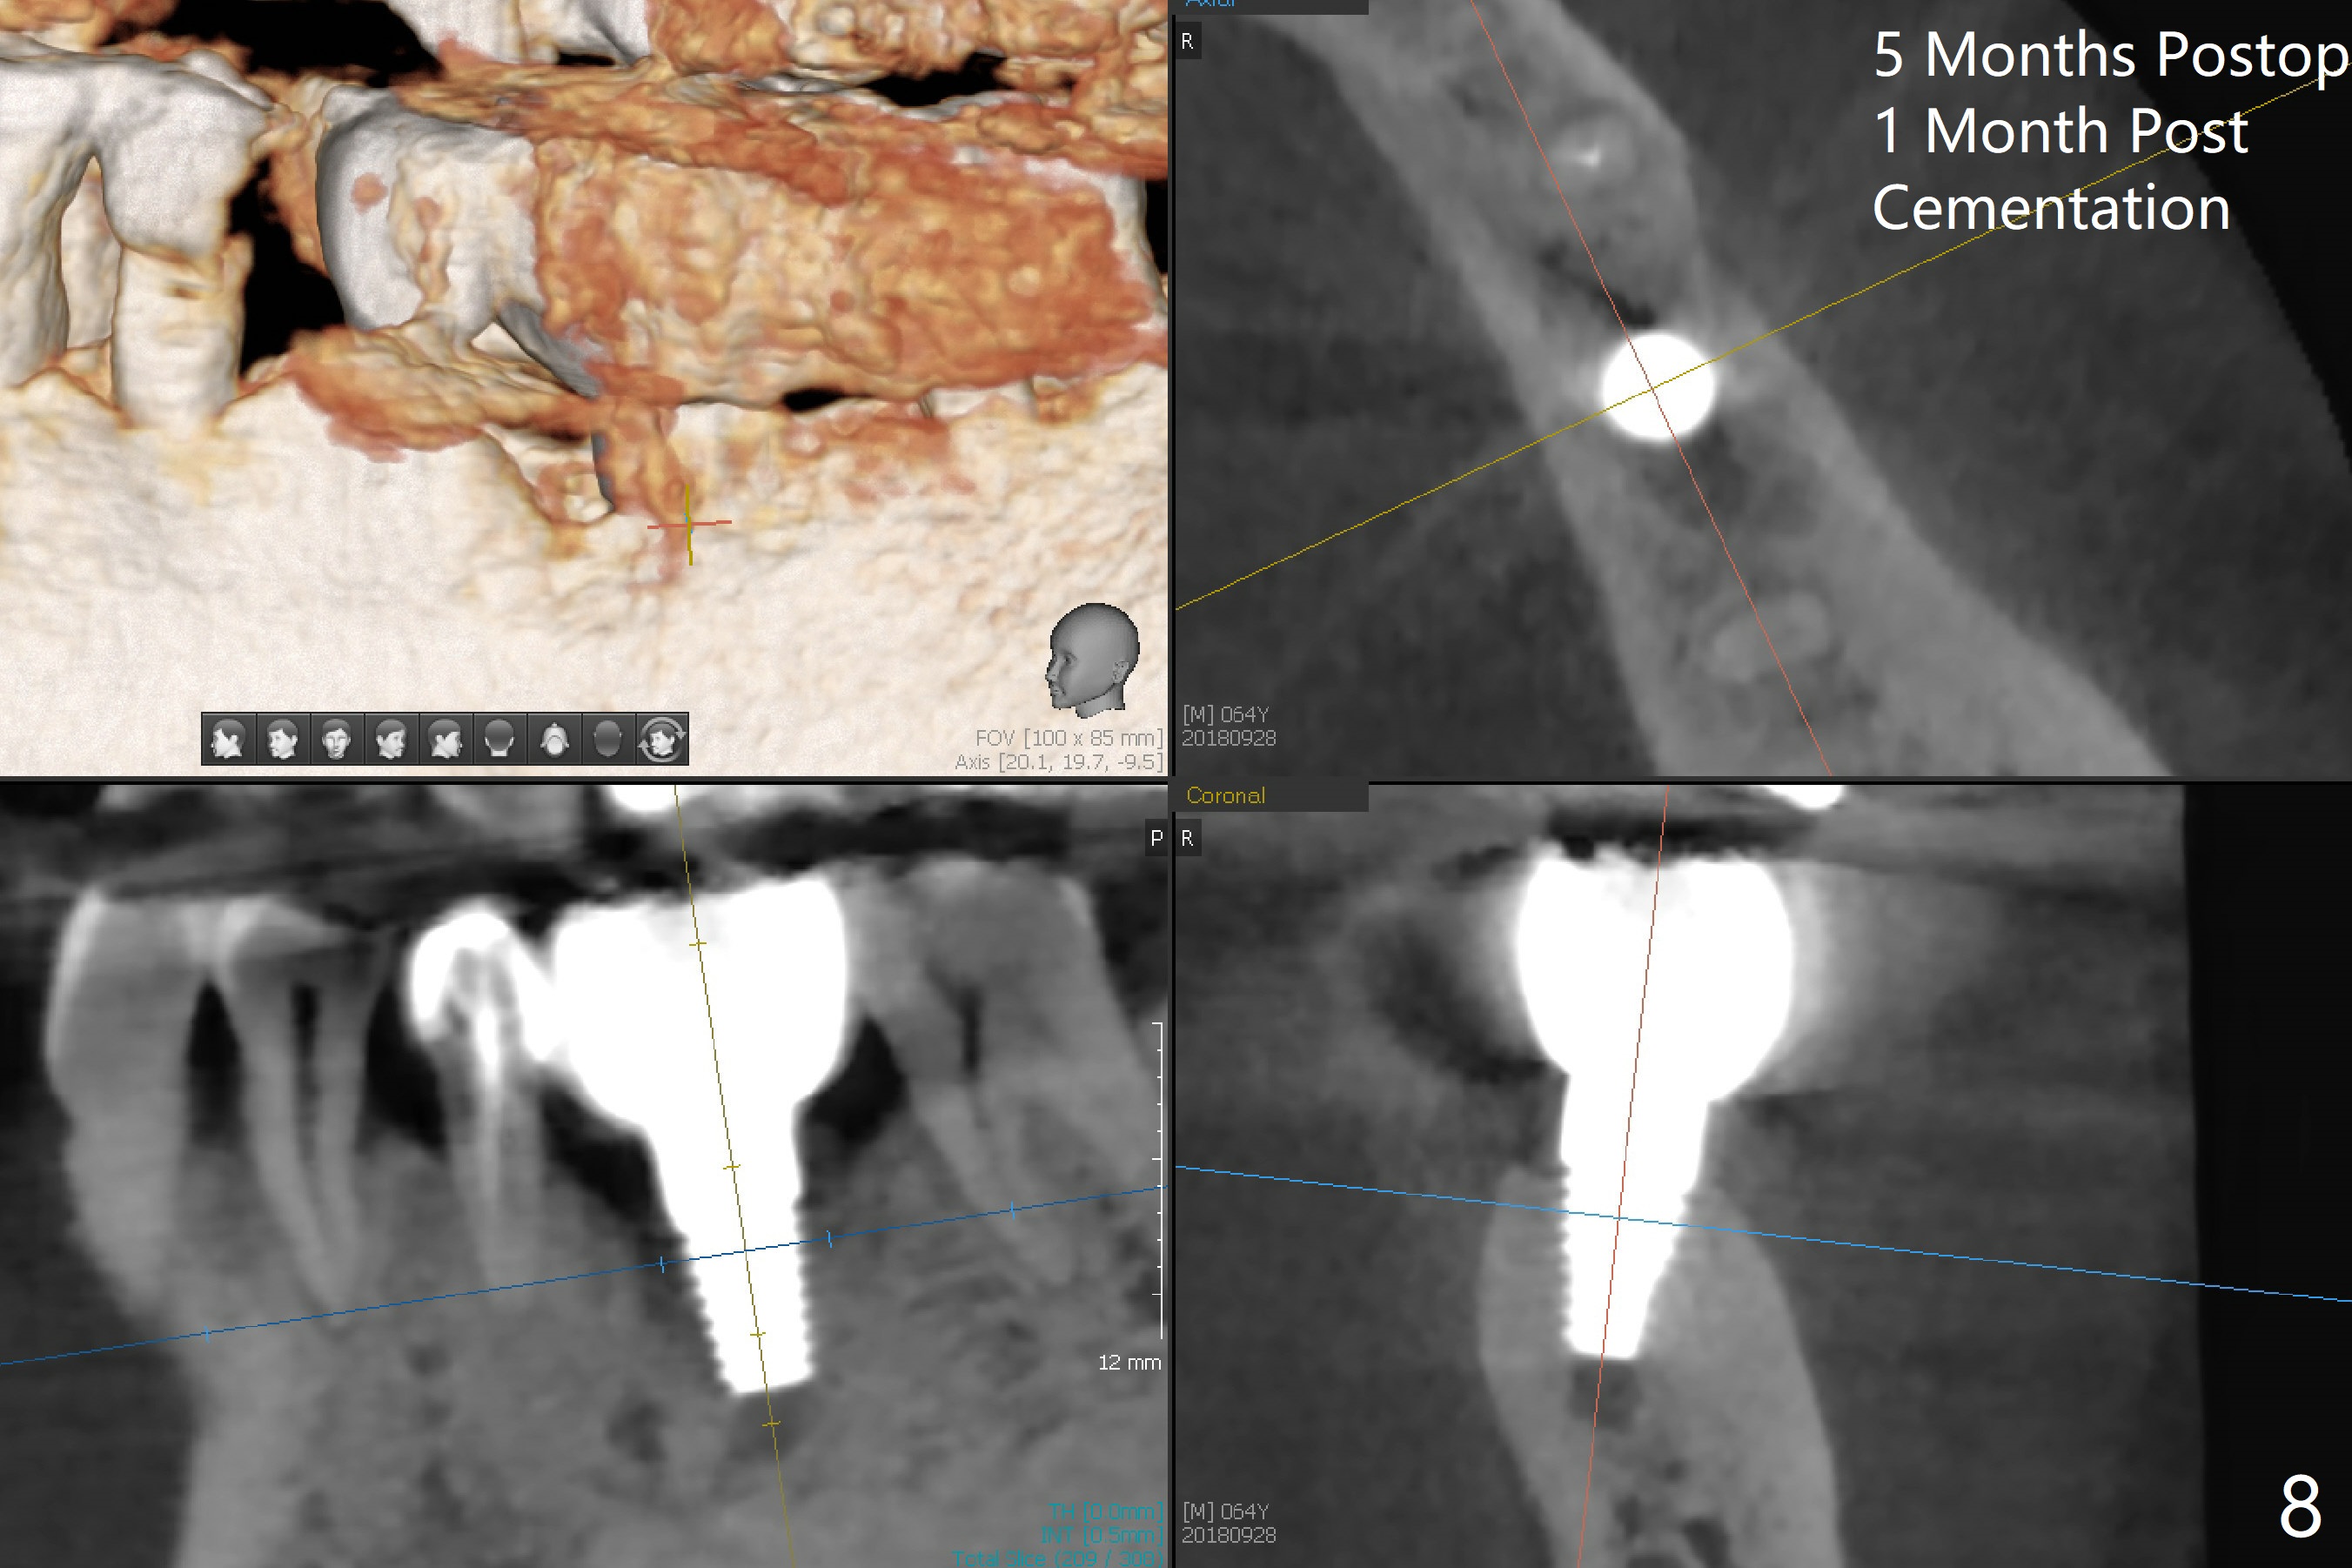

After extraction of the tooth #19 with mesial root fracture (Fig.1 ^) and curettage, the initial osteotomy in the septum is found to need to be distalized (Fig.2 arrow). Following sequential osteotomy, a 5x17 mm tap cannot reach the expected depth (Fig.3 yellow dashed line) because of the dense bone. A shorter implant is placed with >60 Ncm (Fig.4). An immediate provisional is fabricated after placement of a 4.5x5 mm abutment and Vanilla/Osteogen graft (Fig.5 *). The mesial and distal sockets heal 4 months postop (Fig.6). The bone density in the mesial and distal sockets continues to increase when a crown is cemented (~4.5 months postop, Fig.7). The implant at #19 was placed in the middle of the bone (Fig.8).